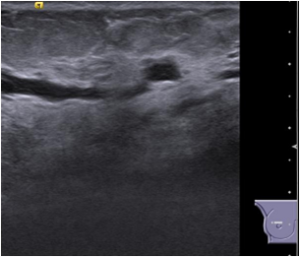

Bilateral Mammograms revealed increased reticular densities in the upper half of the right breast. A 16 mm well defined nodule seen in the left subareolar region. BIRADS 3/4 Bilateral breast ultrasound revealed extensively dilated ducts showing thickened walls and intra ductal contents corresponding to the increased reticular densities on the mammogram of right breast. Left breast revealed a 17 x 10 mm well defined low echogenic lesion with posterior enhancement in the left subareolar region. BIRADS 3 MRI showed segmental clumped / clustered ring enhancement extending from 10 to 2 O’ clock position in the right breast with extensive ductal branching and intraluminal contents extending till the nipple suspicious for DCIS. Left breast revealed a benign 16 x 14mm well defined nodule in the lower inner quadrant close to the nipple. BI-RADS-4.